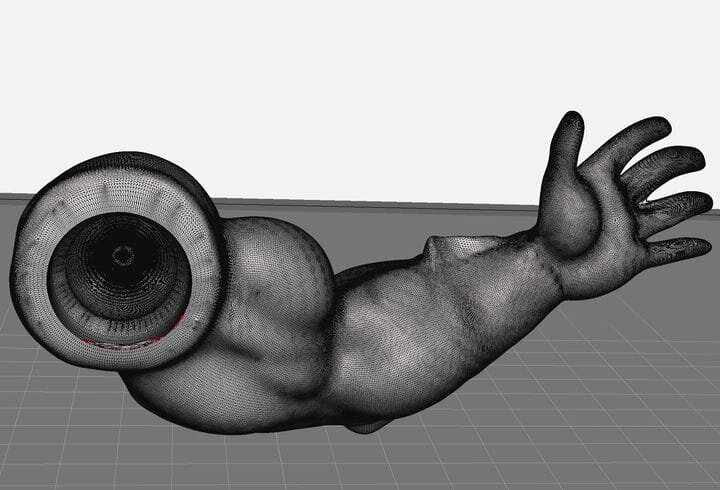

A research paper describes the “Pedi-knee”, a 3D printed prototype of a pediatric knee joint.

children